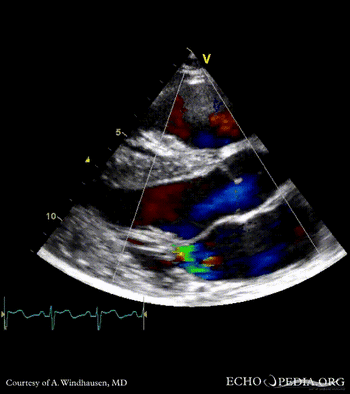

Severe Hypertrophic Cardiomyopathy (HCM)

Case description: Severe Hypertrophic Cardiomyopathy (HCM)

Courtesy of: A. Windhausen, AMC, The Netherlands